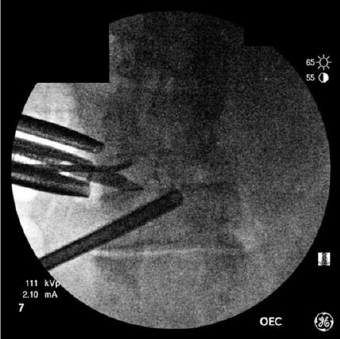

A retrospective review of prospectively collected data was undertaken at a single site. Due to the retrospective nature of the study there was no need to account for failure of patient followup. All cases were completed by a single surgeon at two locations to allow for the different radiological viewing methods. Patients self-selected their hospital based solely on availability and location. From Oct 2018 through July 2019, a total of 68 patients were treated with either single-level or two-level lumbar interbody fusion. The standard low-dose fluoroscopic setting was applied for intraoperative imaging using a GE OEC 9800 c-arm for 34 patients and low-dose capture combined with real-time imageenhancement software (LessRay®, NuVasive, Inc.) was used for 34 patients. The image-enhancement software also included surgical efficiency tools (e.g., tracking to reduce/eliminate scouting shots). All patients were treated in the lateral position for both interbody fusion and bilateral pedicle screw and rod fixation. Lateral (single position surgery) is defined as both anterior and posterior access to the spine without flipping the patient intraoperatively. Therefore, exclusion criteria would include anterior instrumentation or unilateral posterior fixation. Lateral interbody fusion was performed using either transpsoas lateral interbody fusion (XLIF®, NuVasive, Inc.) or lateral-position Anterior Lumbar Interbody Fusion (ALIF) approaches. Screws were placed percutaneously in all cases. Differences in radiation requirements between the two groups was determined by exposure time and mGy emission (Figure 1).

Figure 1: Low-dose pulse image in the AP plane during lateral interbody fusion. Note that the endplates and pedicles are difficult to identify appropriately. Risk of endplate injury, or aberrant screw placement is a concern.